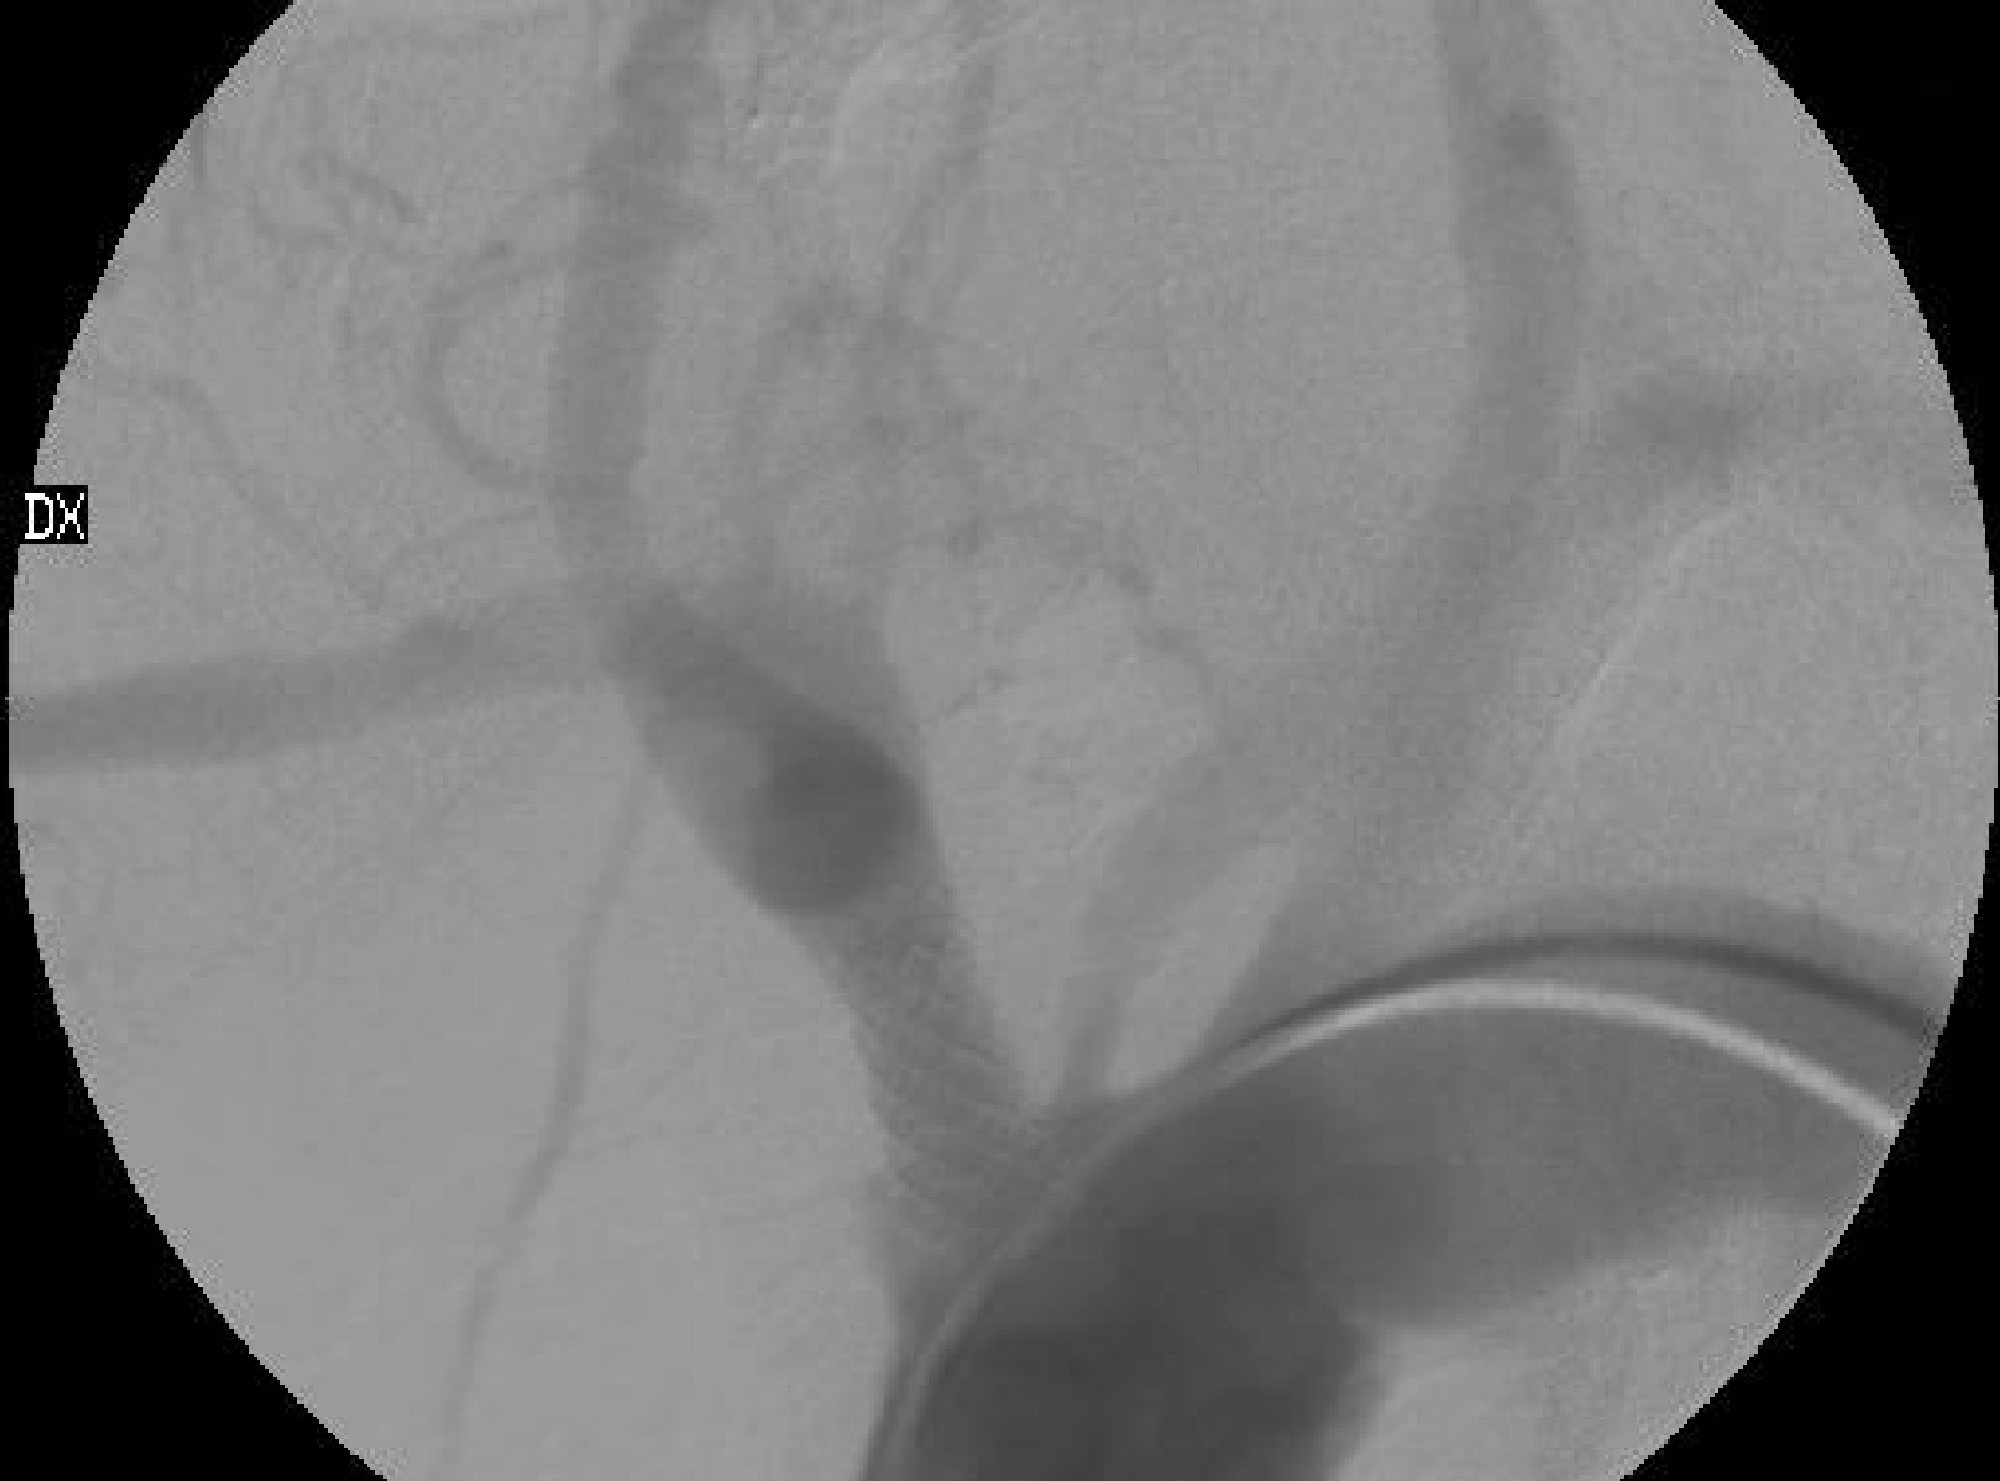

Figure 3 Innominate artery PTA followed by stenting implantation in a 66-year-old man.

(A): Angiography showed a 90% stenosis of the innominate artery.

(B): Final angiography: the stenosis was dilated with an angioplasty balloon of 5 mm of diameter, then a traditional stent was implanted.